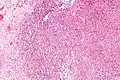

Intermed. mag. Intermed. mag.